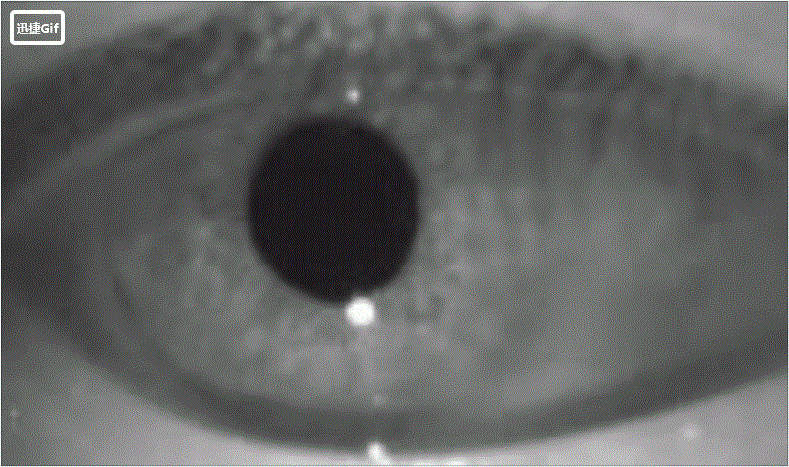

经过神经内科和眼科专家联合会诊认为,造成王女士目前头晕和视物晃动感的主要原因是脑干梗死引起的眼球震颤和眼位偏斜,并且通过眼震电图检查确认了上述病因。那么怎样才能治愈这种病理性的眼球震颤呢?

患者眼震视频